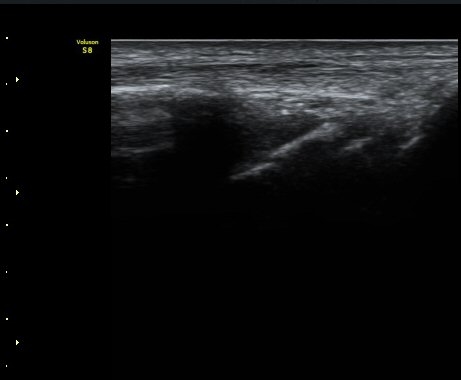

ÃÊÀ½ÆÄ °Ë»ç

¼Õ¸ñÀÇ Á¾´Ü

ÁÖ»ó°ñ ¼±»ó°ñÀýÀº ´Ü¼ø¹æ»ç¼± ÃÔ¿µ ½Ã È®ÀεÇÁö ¾ÊÀº °æ¿ì°¡ ¸¹Àºµ¥ ÀÌ ¶§ ÃÊÀ½ÆÄ

°Ë»ç°¡ ÁÖ»ó°ñ °ñÀý Áø´Ü¿¡ ¸Å¿ì À¯¿ëÇÏ´Ù. ±×·¯¹Ç·Î ¼Õ¸ñ ´ÙÄ£ ÈÄ Áö¼ÓÀûÀÎ ÅëÁõÀ»

È£¼ÒÇϰí ÁÖ»ó°ñ ºÎÀ§ ¾ÐÅëÀ» º¸ÀÌ´Â °æ¿ì ÃÊÀ½ÆÄ°Ë»ç¸¦ ½ÃÇàÇÏ¿© ÁÖ»ó°ñ °ñÀý ¿©ºÎ¸¦

È®ÀÎÇØ¾ß ÇÑ´Ù.

ÃÊÀ½ÆÄ°Ë»ç¸¦ ½ÃÇàÇÒ ¼ö ¾ø´Â °æ¿ì´Â ÄÄÇ»ÅÍ ÃÔ¿µ°Ë»ç¸¦ ÁÖ»ó°ñ °ñÀýÀ» È®ÁøÇÒ ¼ö ÀÖ´Ù.